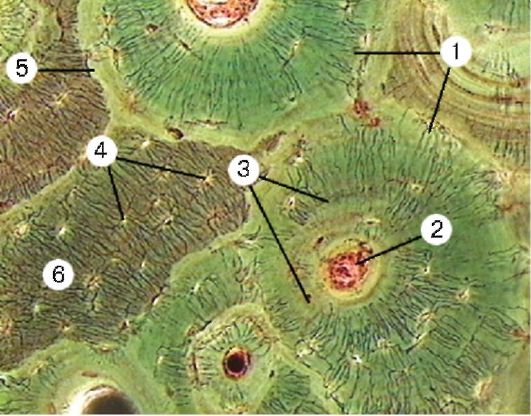

Структура грубоволокнистой костной ткани: наглядные примеры